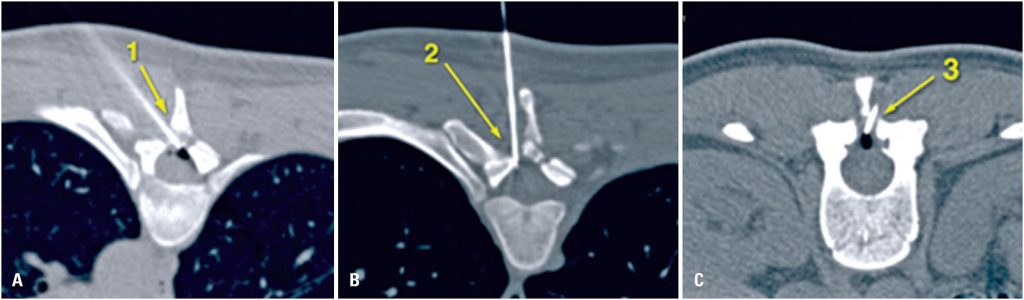

Mammoplasty is commonly performed under epidural anesthesia combined with intravenous sedation; however, this carries a risk of dural puncture and post-dural puncture headache. Successful treatment is often achieved with opioids, non-steroidal anti-inflammatory drugs, and caffeine. When conservative treatment fails, an epidural blood patch should be performed; this procedure has a high resolution rate. We report the case of a patient who developed a post-dural puncture headache 25 days after elective breast implant replacement performed under thoracic epidural anesthesia combined with intravenous sedation. The post-dural puncture headache was refractory to conservative treatment and the first epidural blood patch was unsuccessful. This case represents an exceptionally rare presentation of post-dural puncture headache, marked by a delayed onset of nearly four weeks and requiring a second epidural blood patch for symptom resolution.